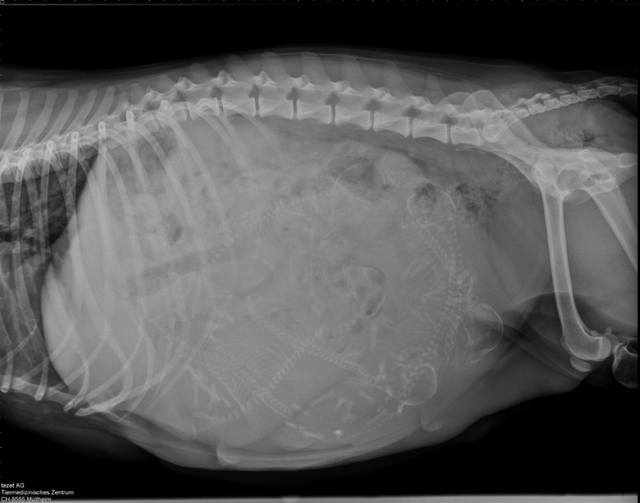

Wie bei jedem unserer Würfe waren wir auch dieses Mal vor der Geburt nochmals beim Tierarzt zum Röntgen. Dabei konnten wir 6 Zwerge auf dem Bild erkennen. Die Freude war riesig.